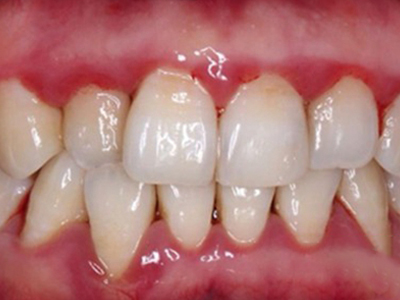

牙龈退缩牙根暴露出现黑斑图

牙龈退缩患者的上排多颗牙齿处的牙龈出现回缩,从而导致牙根外露,外露的牙根上存在黑色的牙菌斑、牙结石,伴有口臭、牙根面敏感等症状。